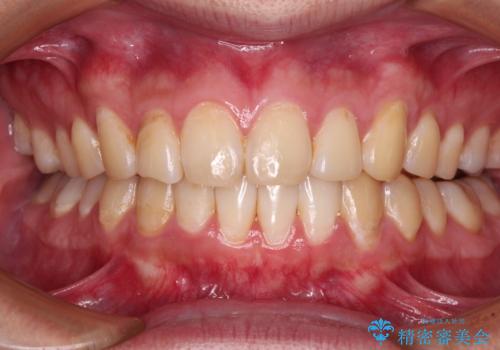

写真より左側臼歯の咬合がタイトではないことが分かりますが、こちらは保定期間に徐々に咬合させていくこととしました。